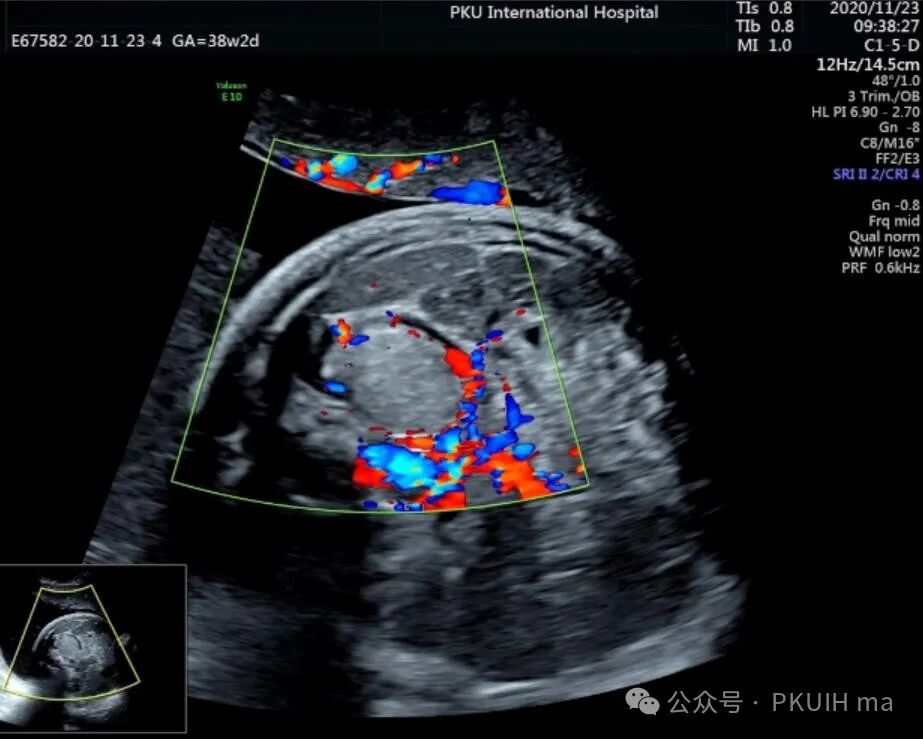

上图是一例在孕晚期发现的肾上腺占位,生后病理证实为神经母细胞瘤的患儿,生后及时做了治疗预后非常好,目前宝宝各项指标都很好。

同时在孕晚期也发现孕妇羊水增多

这几年我们在孕晚期发现有3例神经母细胞瘤胎儿,预后都很好。在孕晚期超声中建议常规扫查下胎儿双肾区